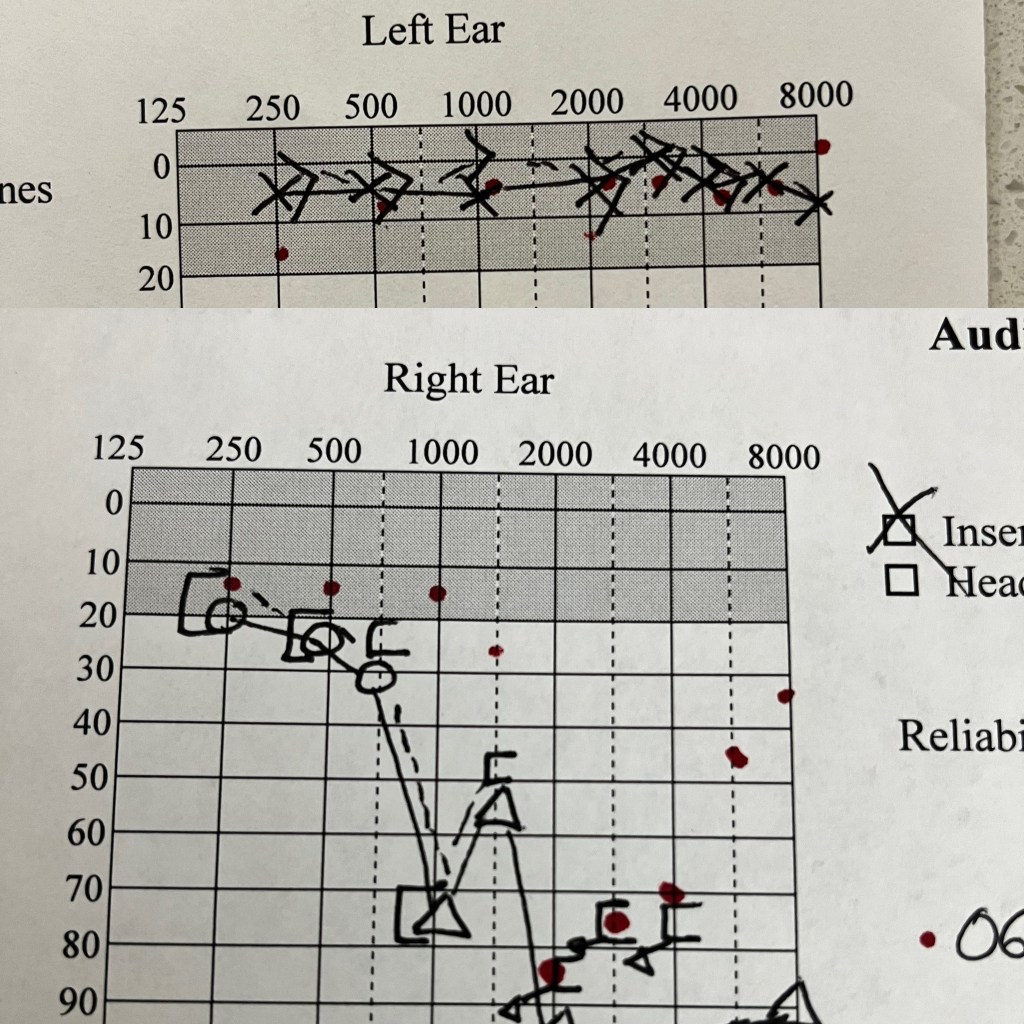

That’s my head! I’ve been losing hearing in my right ear for about two years now. I had it checked over a year ago and we agreed to keep an eye on it. Life got in the way (don’t do that!!!) and I put off the recheck. They had me get an MRI and sure enough, there’s an intruder in there who will need to be evicted via surgery.

Ummmm… right ear? You good?

WHEN? When is your surgery? That has been the big question. I have to get a CT scan on Monday and then hopefully we’ll be able to kick this tumor out. She’s gotten quite comfortable in there, which makes the surgery pretty involved. They can’t preserve my hearing, but they have to be careful around those other nerves.

We will try to keep everyone updated the best we can – the good, the hard and the ugly. I’m gonna have a rocking new haircut involving a shaved side by my right ear. I’m also going to be in the hospital for about 4 days. Then it is recovery and physical therapy time. This thing has damaged my hearing in the one ear permanently and there’s a good chance it will temporarily affect my vestibular nerve – leaving me quite dizzy.